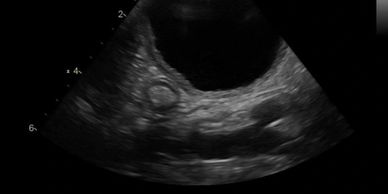

An evaluation of every abdominal organ for size, margination, echotexture, and neoplasia. All standard abdominal measurements will be acquired according to the current ACVR protocol

Screening of the gastrointestinal tract for foreign material

Evaluation and measurements of the intestinal wall layers. Includes screening for intestinal masses, inflammatory disease, and gastrointestinal lymphoma

Screening of the the urinary and biliary tract for stones, accumulated material, obstructions, or evidence of congenital defects